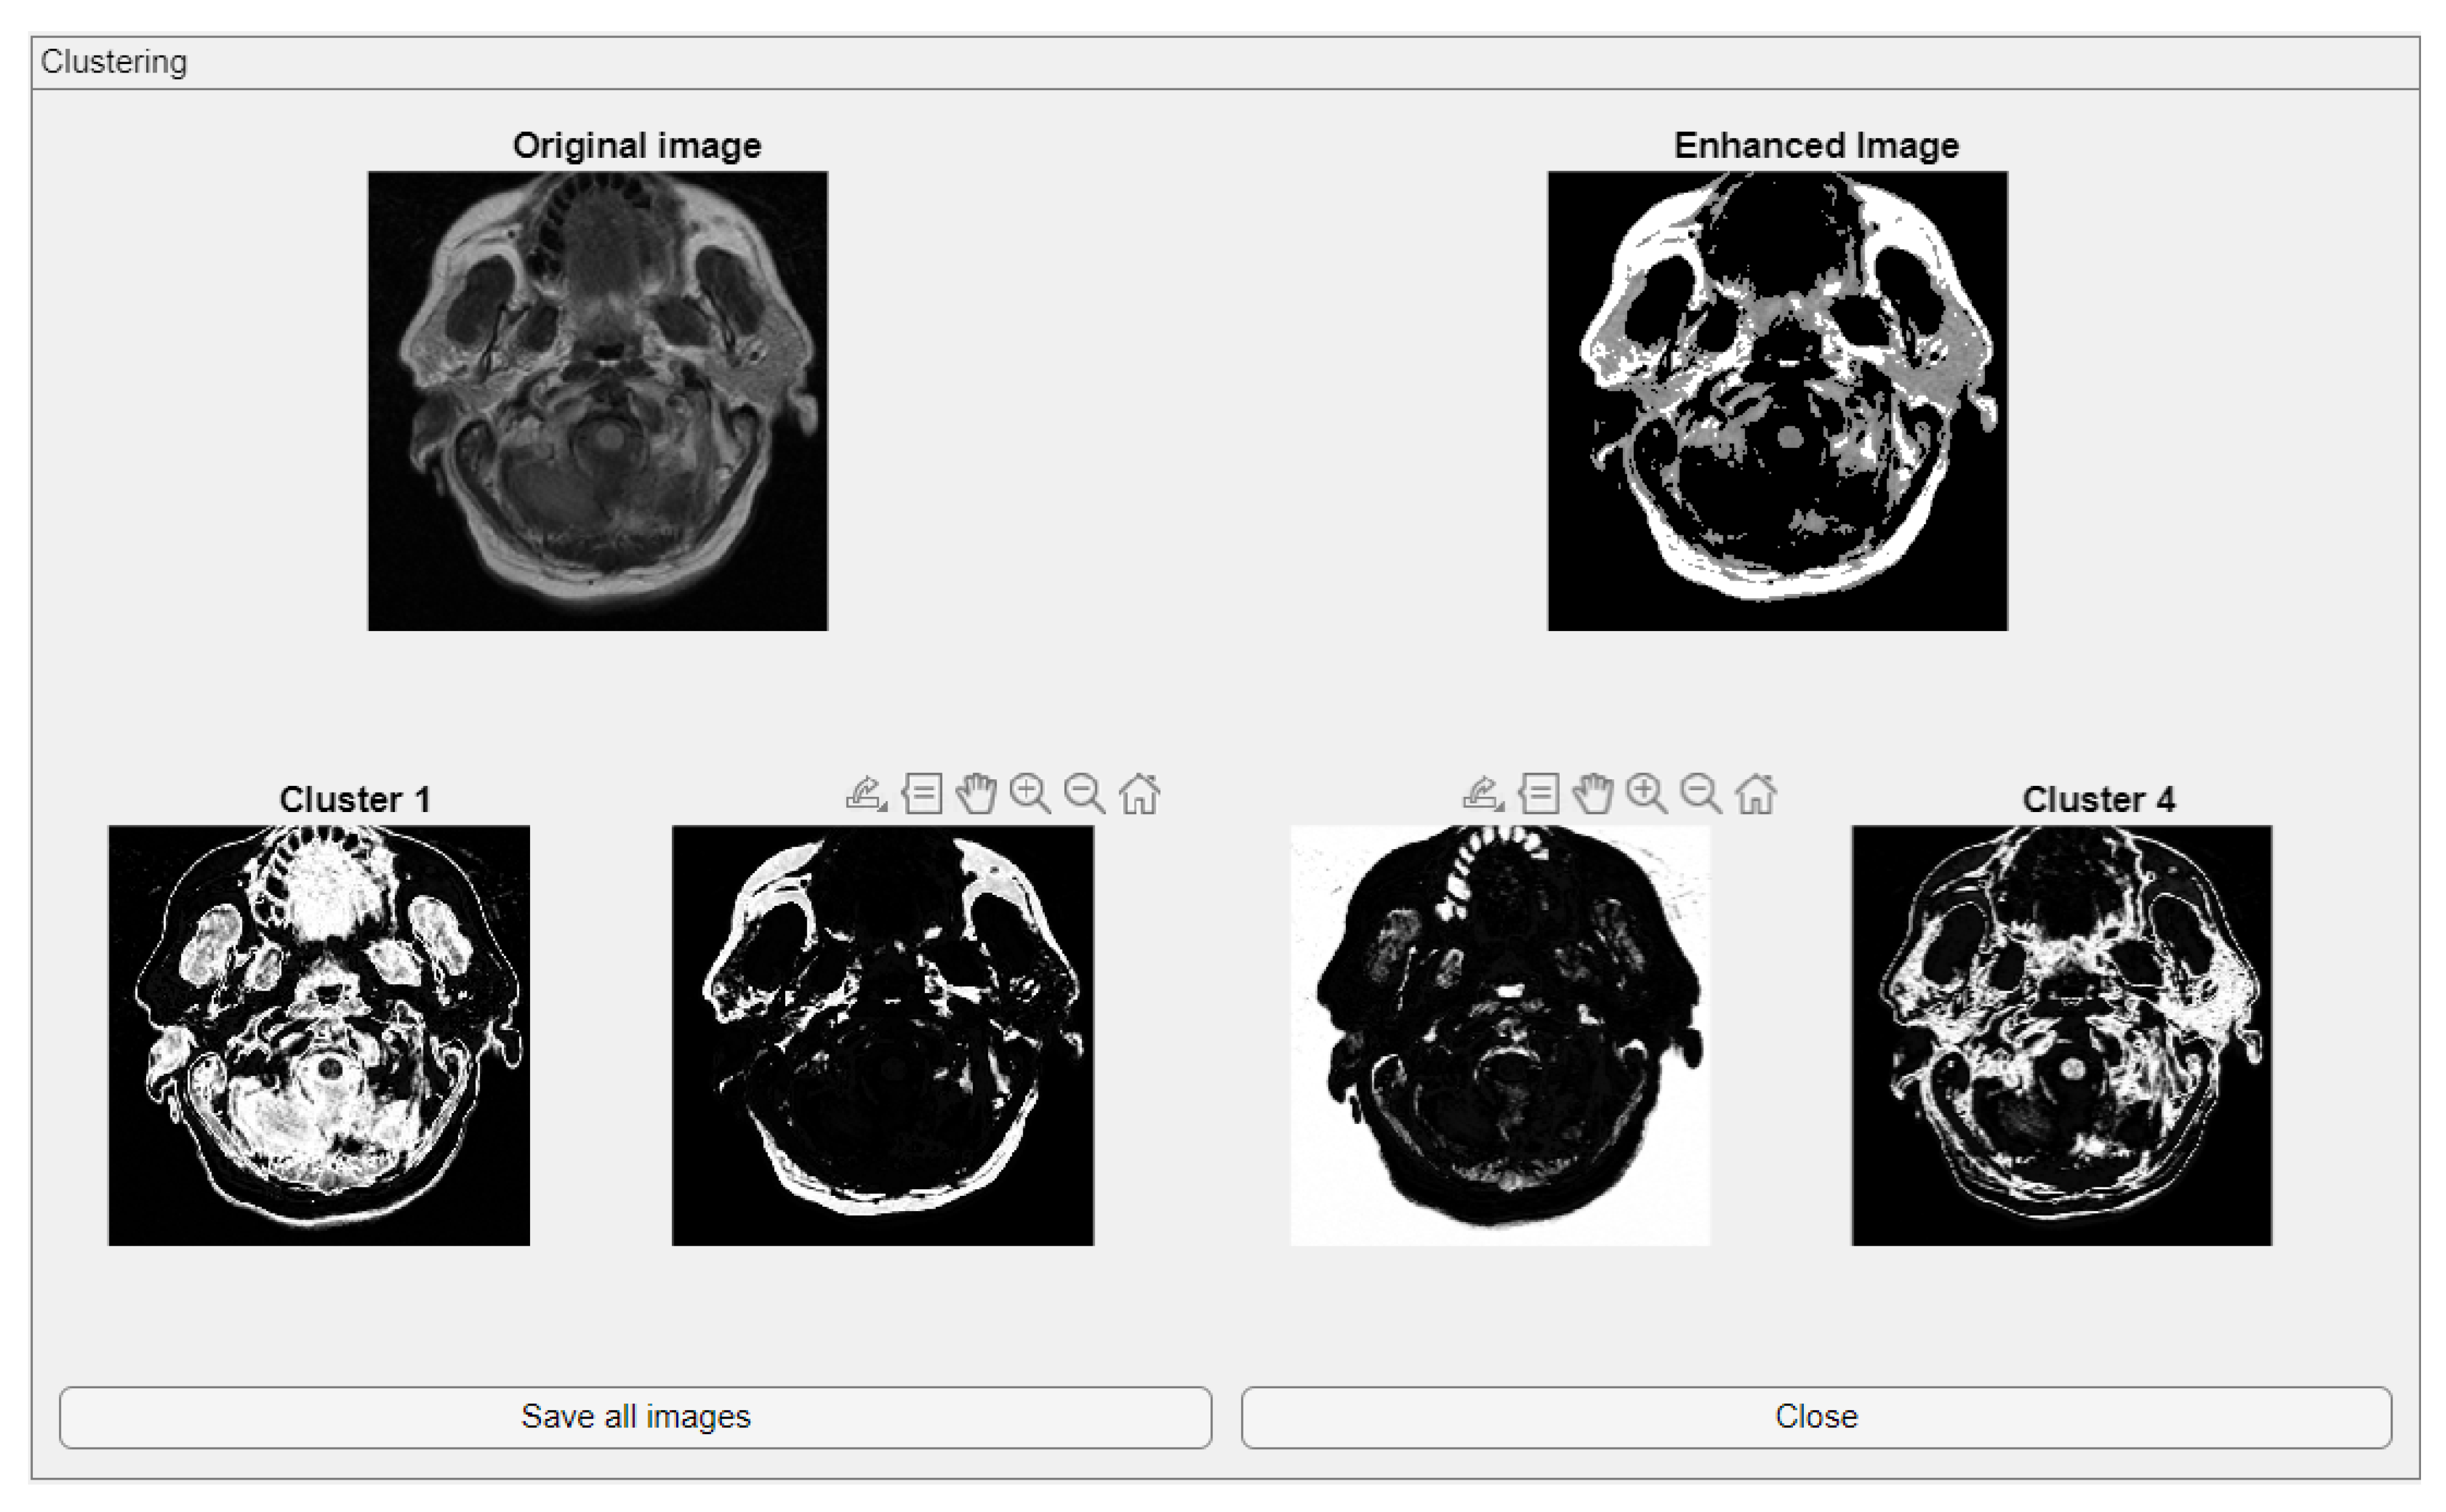

2.2. Clustering

The Clustering module integrates fuzzy C-means (FCM) clustering for unsupervised image segmentation [37]. This functionality supports the automatic classification of image regions based on pixel intensity distributions while accommodating partial membership, which is particularly suitable for medical images where tissue boundaries may not be well defined. The module also provides the option to save both the clustered image and the enhanced image, enabling users to store intermediate and final processing results for future reference or external evaluation. This added functionality ensures that the outputs of the clustering process can be efficiently archived or used in subsequent processing steps.

The comparative charts and visual presentation of edges allow for a detailed analysis of each algorithm’s strengths and weaknesses, offering insight into the trade-offs between edge completeness and false detection rates. Figure 4 illustrates the fuzzy C-means (FCM) clustering results obtained from the four case studies: CS1, CS2, DU1, and DU2. Each subfigure (A, B, C, and D) presents the following sequence:

-

Original Image: The initial input image from the dataset.

Enhanced Image: The result after applying image enhancement techniques to improve contrast and feature visibility, likely to support better clustering outcomes.

Clusters 1 to 4: The segmentation outputs, where the image has been partitioned into four distinct clusters. Each cluster highlights different regions based on pixel similarity, potentially corresponding to anatomical structures, tissues, or specific features of interest within the medical images.

Key Observation: Figure 4 and Figure A1 collectively showcase the clustering module’s capacity to aid in visual discrimination and structural interpretation across the studied medical cases.

Figure 4. Clustering with fuzzy C-means (FCM) results within iMIA platform: The clusters emphasize various structural and textural components, with some clusters isolating specific regions with clear edges and others focusing on more homogeneous areas. The segmentation reveals critical areas with varying intensity patterns, possibly indicative of different tissue types or pathological regions: TCGA_CS_4941_19960909_3 (CS1) (additional results are shown in Figure A1).